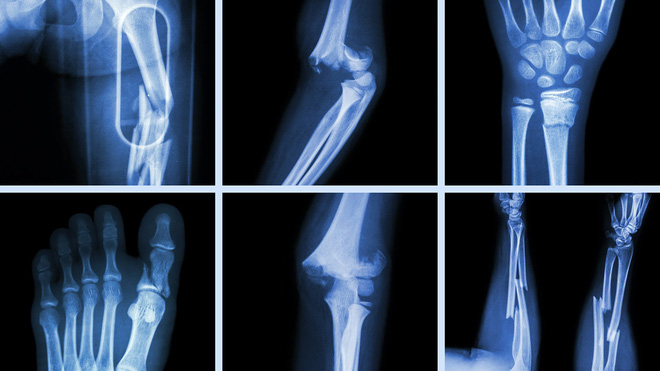

Hỏi bệnh sử và khám thực thể. Chụp X-quang sẽ xác định chẩn đoán.

Click vào ảnh để xem 4 hình ảnh minh họa